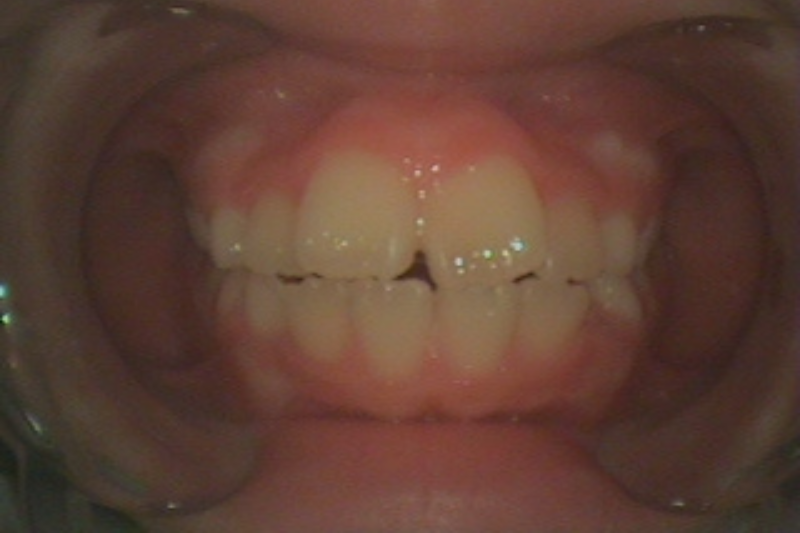

症例2

Before

症例2 治療前

After

症例2 治療後

年齢・性別 12歳・女の子

治療内容 マイオブレイス

治療期間 3年10ヶ月

費用 400,000円(税込)

主なリスク 矯正装置の装着時に違和感や痛みが生じる場合があります。

装置の使用状況により治療期間が延長する場合があります。

治療後、保定装置を使用しない場合は後戻りする可能性があります。

治療結果には個人差があります。